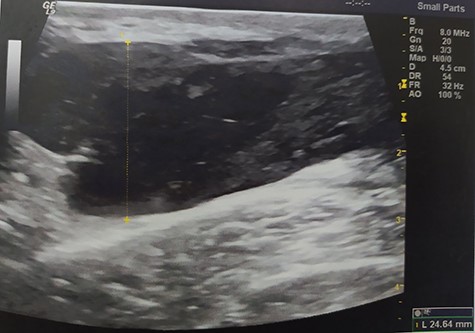

A 55-year-old Caucasian male proceeded to our institution complaining about irreducible swelling of the right iliac fossa and constant discomfort, over the course of a year. His medical history revealed that he slapped against a blunt surface of a furniture a year ago and injured his right groin and pelvis. Due to the accident and the subsequent painful swelling, the patient underwent immediately a pelvic ultrasound the detected an acute hematoma with a diameter of 52 mm into the fatty tissue of the right pelvic fossa (Fig. 1). Ten months after the accident, due to the irreducible swelling, the patient underwent another ultrasound revealing a nonorganized hematoma with thrombotic features (sized as 25 × 60 × 58 mm) (Fig. 2).

Pelvic ultrasound indicating an acute hematoma into the fatty tissue of the right iliac fossa.